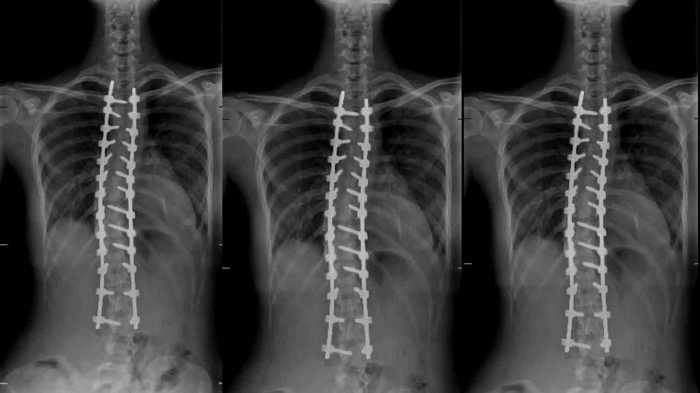

Aynı zamanda omurga eğriliği olarak bilinen skolyozda ameliyat kararını belirleyen faktörlerden birinin ileri derecede eğrilik olduğunu dile getiren Opr. Dr. Uysal, "Omurga eğriliğinin 40 derece ve üzeri olduğu hastalara, ameliyat dışı tedavilerin yeterli olmaması durumunu ve şiddetli ağrıların olup olmadığını da değerlendirerek cerrahi tedavi önermekteyiz. Robotik omurga cerrahisinde kullandığımız yeni nesil MAZOR robotu ile ameliyat öncesi veya ameliyat sırasında, her hastanın omurga yapısına özel olarak planlama yapabilmekteyiz. Buradaki hedefimiz omurlara vida ve rod adını verdiğimiz metal çubuklardan oluşan implantlar yerleştirerek eğriliğin düzeltilmesi ile düzeltilen bölgedeki omurların birbiriyle kaynaşmasını sağlamaktır. Robotik omurga cerrahisinin buradaki inanılmaz etkisi, implantların yerleştirileceği noktaları son derece hassas ve detaylı hesaplamalarla gerçekleştirerek en iyi açının sağlanması ve minimum hata ile ameliyatın tamamlanmasıdır. Ameliyat sırasında yapılan işlemleri eş zamanlı ve en önemlisi 3 boyutlu olarak takip edebiliyor olmamız ise robotik omurga cerrahisinin bizlere sağladığı bir diğer avantajdır" şeklinde ifade etti.